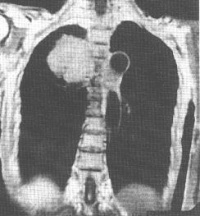

纵隔也是好发部位之一,受侵的纵隔淋巴结,可以是单个的淋巴结肿大,也可以是多个淋巴结融合成巨块,外缘呈波浪状,侵犯一侧或双侧纵隔,以后者较多见。

恶性淋巴瘤约 2% 左右可发生于肺部,表现为肺野内边界清楚的圆形或分叶状阴影,患者自觉症状很少。有的患者可侵犯肺门或纵隔淋巴结,一般很少有上腔静脉压迫征或纵隔肌麻痹,治疗预后也较好。由纵隔侵犯肺部的恶性淋巴瘤多靠近肺门,常常连成一片,可为单侧或双侧性,并常伴有气管旁淋巴结肿大,也易引起压迫症状,其预后不如原发于肺的病例。